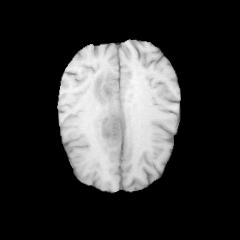

Glioma is a prevalent brain tumor that poses a significant health risk to individuals. Accurate segmentation of brain tumor is essential for clinical diagnosis and treatment. The Segment Anything Model(SAM), released by Meta AI, is a fundamental model in image segmentation and has excellent zero-sample generalization capabilities. Thus, it is interesting to apply SAM to the task of brain tumor segmentation. In this study, we evaluated the performance of SAM on brain tumor segmentation and found that without any model fine-tuning, there is still a gap between SAM and the current state-of-the-art(SOTA) model.